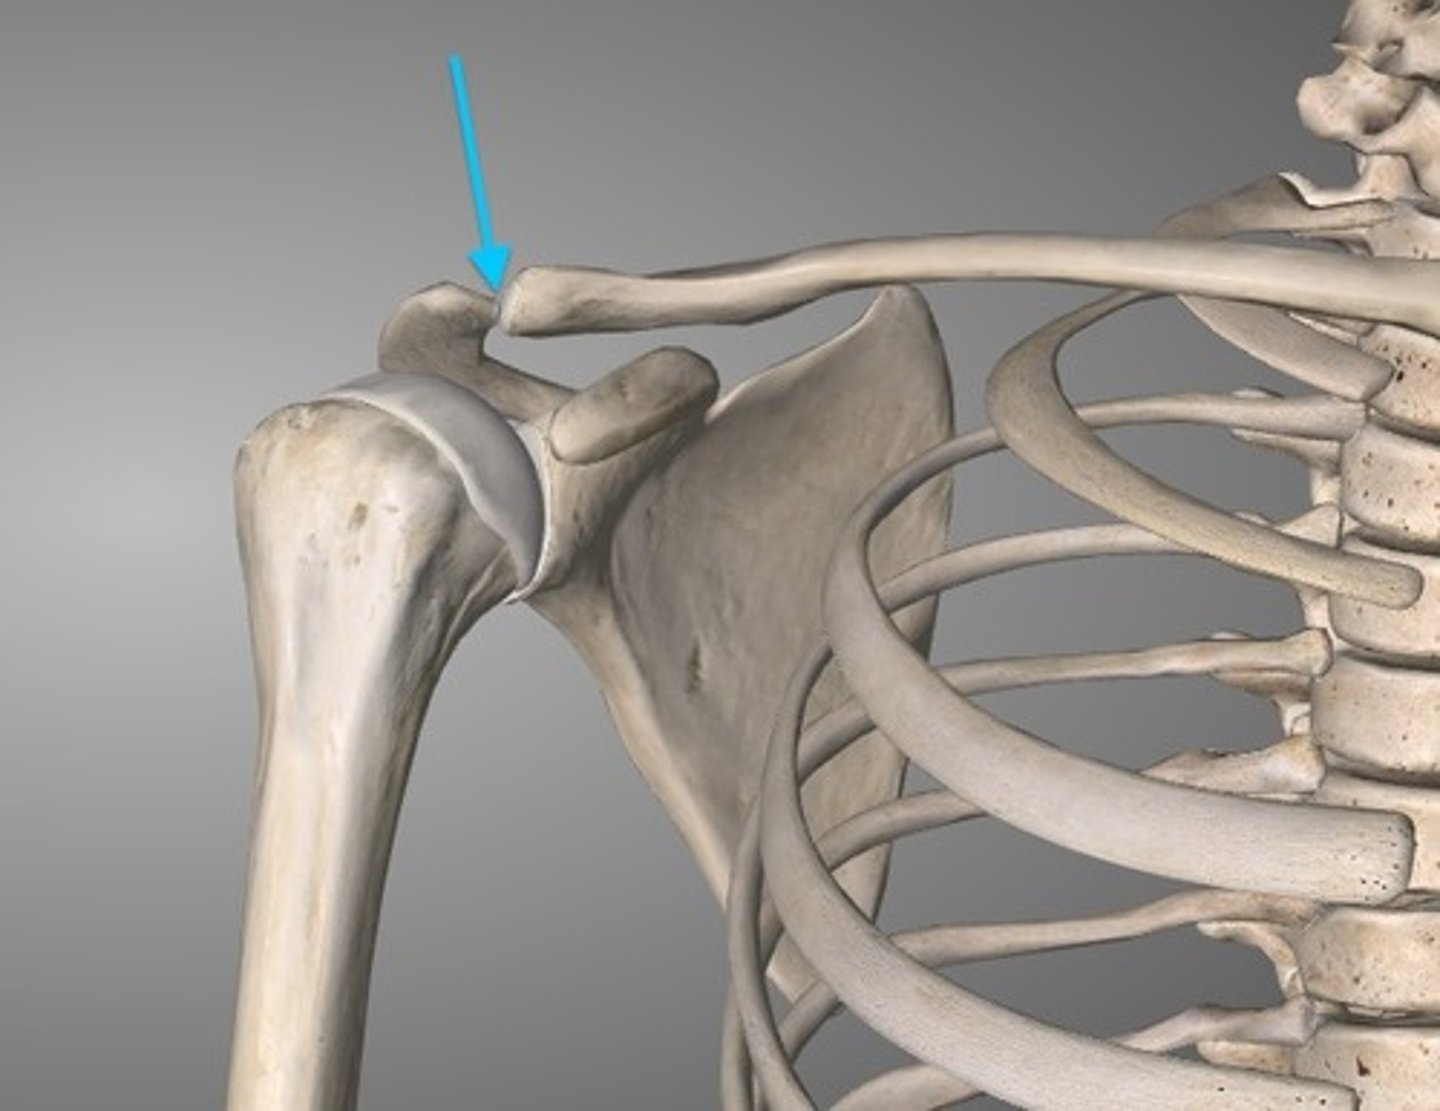

Acromioclavicular joint

the joint where the acromion and the clavicle meet (gliding joint)